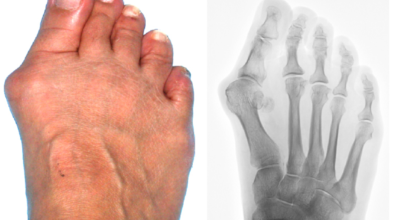

무지외반증은 엄지발가락이 두 번째 발가락 쪽으로 과도하게 휘고, 그와 함께 엄지발가락과 연결된 중족골이 안쪽으로 치우쳐 변형되는 상태입니다. 또한, 발가락이 발등 쪽으로 휘거나 회전하는 삼차원적인 변형을 일으킬 수 있습니다.

이 변형이 심해지면 엄지발가락이 두 번째 발가락과 겹치거나 관절이 탈구되면서 발을 디디는 것이 어려워지기도 합니다. 건강보험심사평가원의 통계에 따르면, 무지외반증 환자는 주로 40대 이상에서 많이 발생하며, 특히 여성 환자가 남성보다 훨씬 많은 비율을 차지한다고 합니다.

무지외반증이 진행되면 육안으로 엄지발가락의 변형이 뚜렷하게 나타납니다. 초기에는 굳은살이 생기고 약간의 통증이 동반될 수 있습니다. 엄지발가락이 돌출된 부위는 신발에 자극을 받아 두꺼워지고 염증이 발생하여 통증이 생깁니다. 발바닥이 휘어지지 않더라도 굳은살 때문에 정상적인 보행이 어려워지고, 심한 경우에는 통증으로 인해 신발을 신는 것조차 힘들어질 수 있습니다. 증상이 계속 악화되면 엄지발가락이 겹쳐지거나 탈구되는 경우도 발생할 수 있습니다.

또한, 엄지발가락이 옆으로 휘어지면서 관절에 비정상적인 압력이 가해져 퇴행성 관절염이 생길 수 있습니다. 엄지발가락이 발바닥의 압력을 지지하지 못하게 되면, 2, 3번째 발가락으로 그 부담이 옮겨져 발바닥에 굳은살이 생기고, 발가락 뼈 사이의 신경이 부풀어 통증을 일으키는 지간신경종이 발생할 수 있습니다.